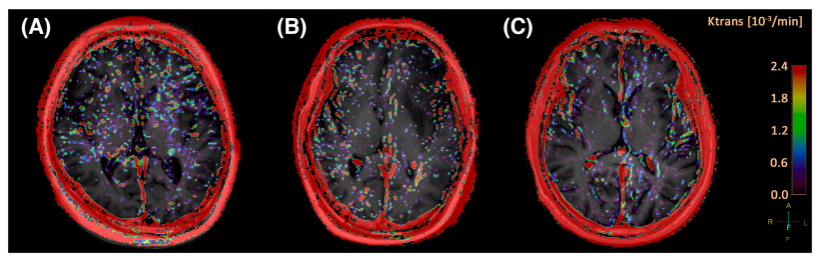

(一)由医院神经重症科与影像科合作发表题为Blood–brain barrier damage and new onset refractory status epilepticus: An exploratory study using dynamic contrast-enhanced magnetic resonance imaging:首次探索癫痫持续状态患者不同脑区血脑屏障受损情况的临床研究论文(第一作者:李惠平,主治医师,神经重症科;通讯作者:袁方,主治医师,神经重症科)。该研究共纳入7例新发难治性癫痫持续状态(NORSE)患者,14例无SE的脑炎患者以及9例健康对照者,运用动态对比增强核磁共振(DCE-MRI)技术分析了6个脑区(双侧海马、基底神经节、丘脑、屏状核、脑室周围白质和小脑)的血脑屏障通透性。结果显示NORSE患者的血脑屏障弥漫性受损,且其基底节和丘脑的血脑屏障受损程度显著高于无SE的脑炎患者。提示基底节和丘脑区血脑屏障的受损在NORSE的病理发展中起着重要作用。研究首次探索了SE患者不同脑区血脑屏障受损情况,为理解NORSE的病理机制、寻找NORSE治疗新靶点提供了理论依据。